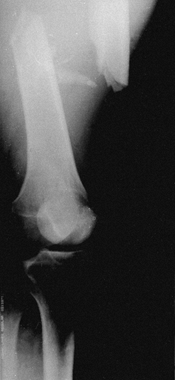

The initial radiograph often points to the degree of soft-tissue injury

and instability. In fractures of the tibia with unstable patterns,

plaster of Paris cast management alone usually results in shortening

equal to that seen on the original radiograph (Fig. 10.10).

Excessive shortening is a hallmark of more severe soft-tissue injury,

and without special measures to prevent shortening, the fracture will

heal in a shortened position. Transverse fractures with good end-to-end

contact are stable against shortening; the challenge is simply to

control angular and rotational deformity, which can usually be done

with a cast or splint (Fig. 10.11).

Figure 10.10.

The amount of shortening seen on the initial postinjury x-rays indicates the degree of soft-tissue stripping that has occurred about the fracture site. |